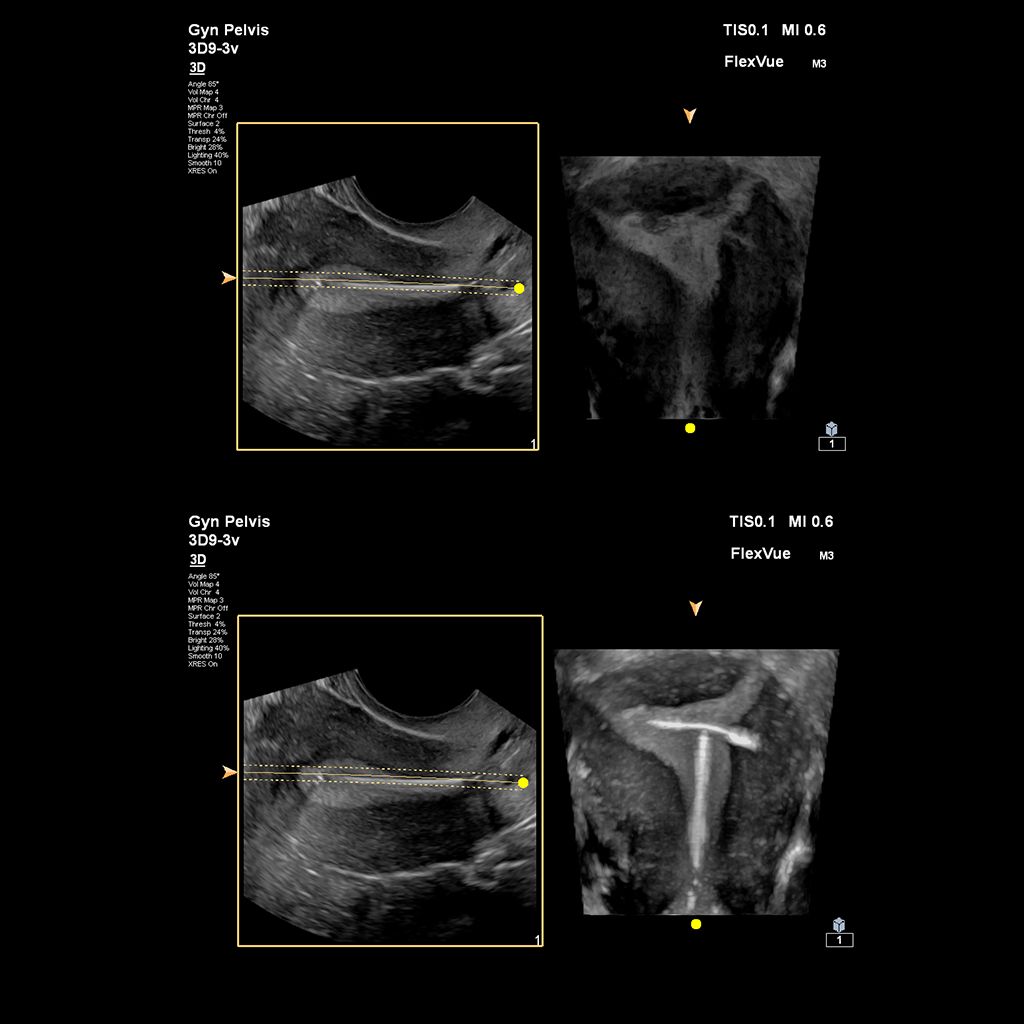

Demonstrated results using FlexVue

It (FlexVue) takes all of the complications out of MPR and manipulation of a surface-rendered volume. By deploying a straight line or a curved trace or continuous trace, we can take a curved image, flatten it out and make it a single planar image.